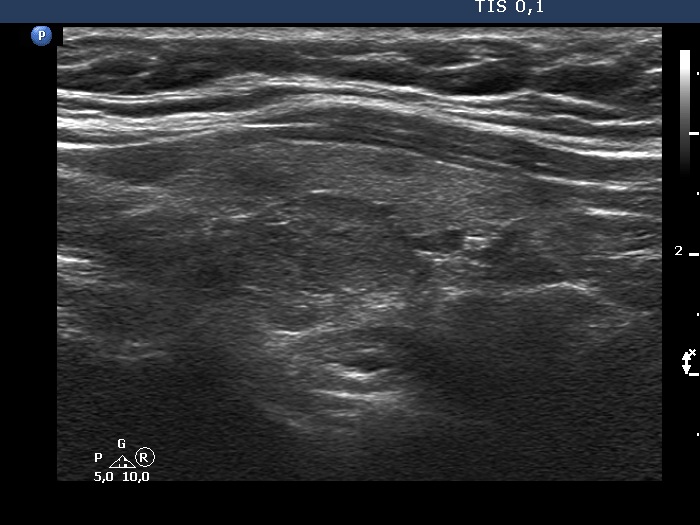

Ultrasonography. The thyroid was echonormal. According to the PET-positive lesion, there was a moderately hypoechoic nodule in the middle-dorsal part of the left lobe. The lesion presented with perinodular blood flow. In the transverse section, it appeared that there was another nodule in the lower pole of the lobe. At the same time, based on the longitudinal section, it was not an oval, nodule-like lesion. The mass proved to be longitudinally elongated in the caudal direction and was avascular.

An anatomical structure running perpendicular to the transducer looks round or oval, and it can look deceptively like a discrete lesion. If this occurs in the thyroid region, it can be mistaken for a nodule. The most common examples of this are the carotid artery, the jugular vein, and the esophagus, the latter usually appears on the dorsal surface of the left lobe of the thyroid gland. The key is always to examine the patient in two perpendicular planes. An examination parallel to the anatomical structure (in this case in the longitudinal section) shows that it is a tube-like, longitudinal structure. In this case, it was very likely a dorsal muscle.

A muscle used to be avascular on Doppler mode.